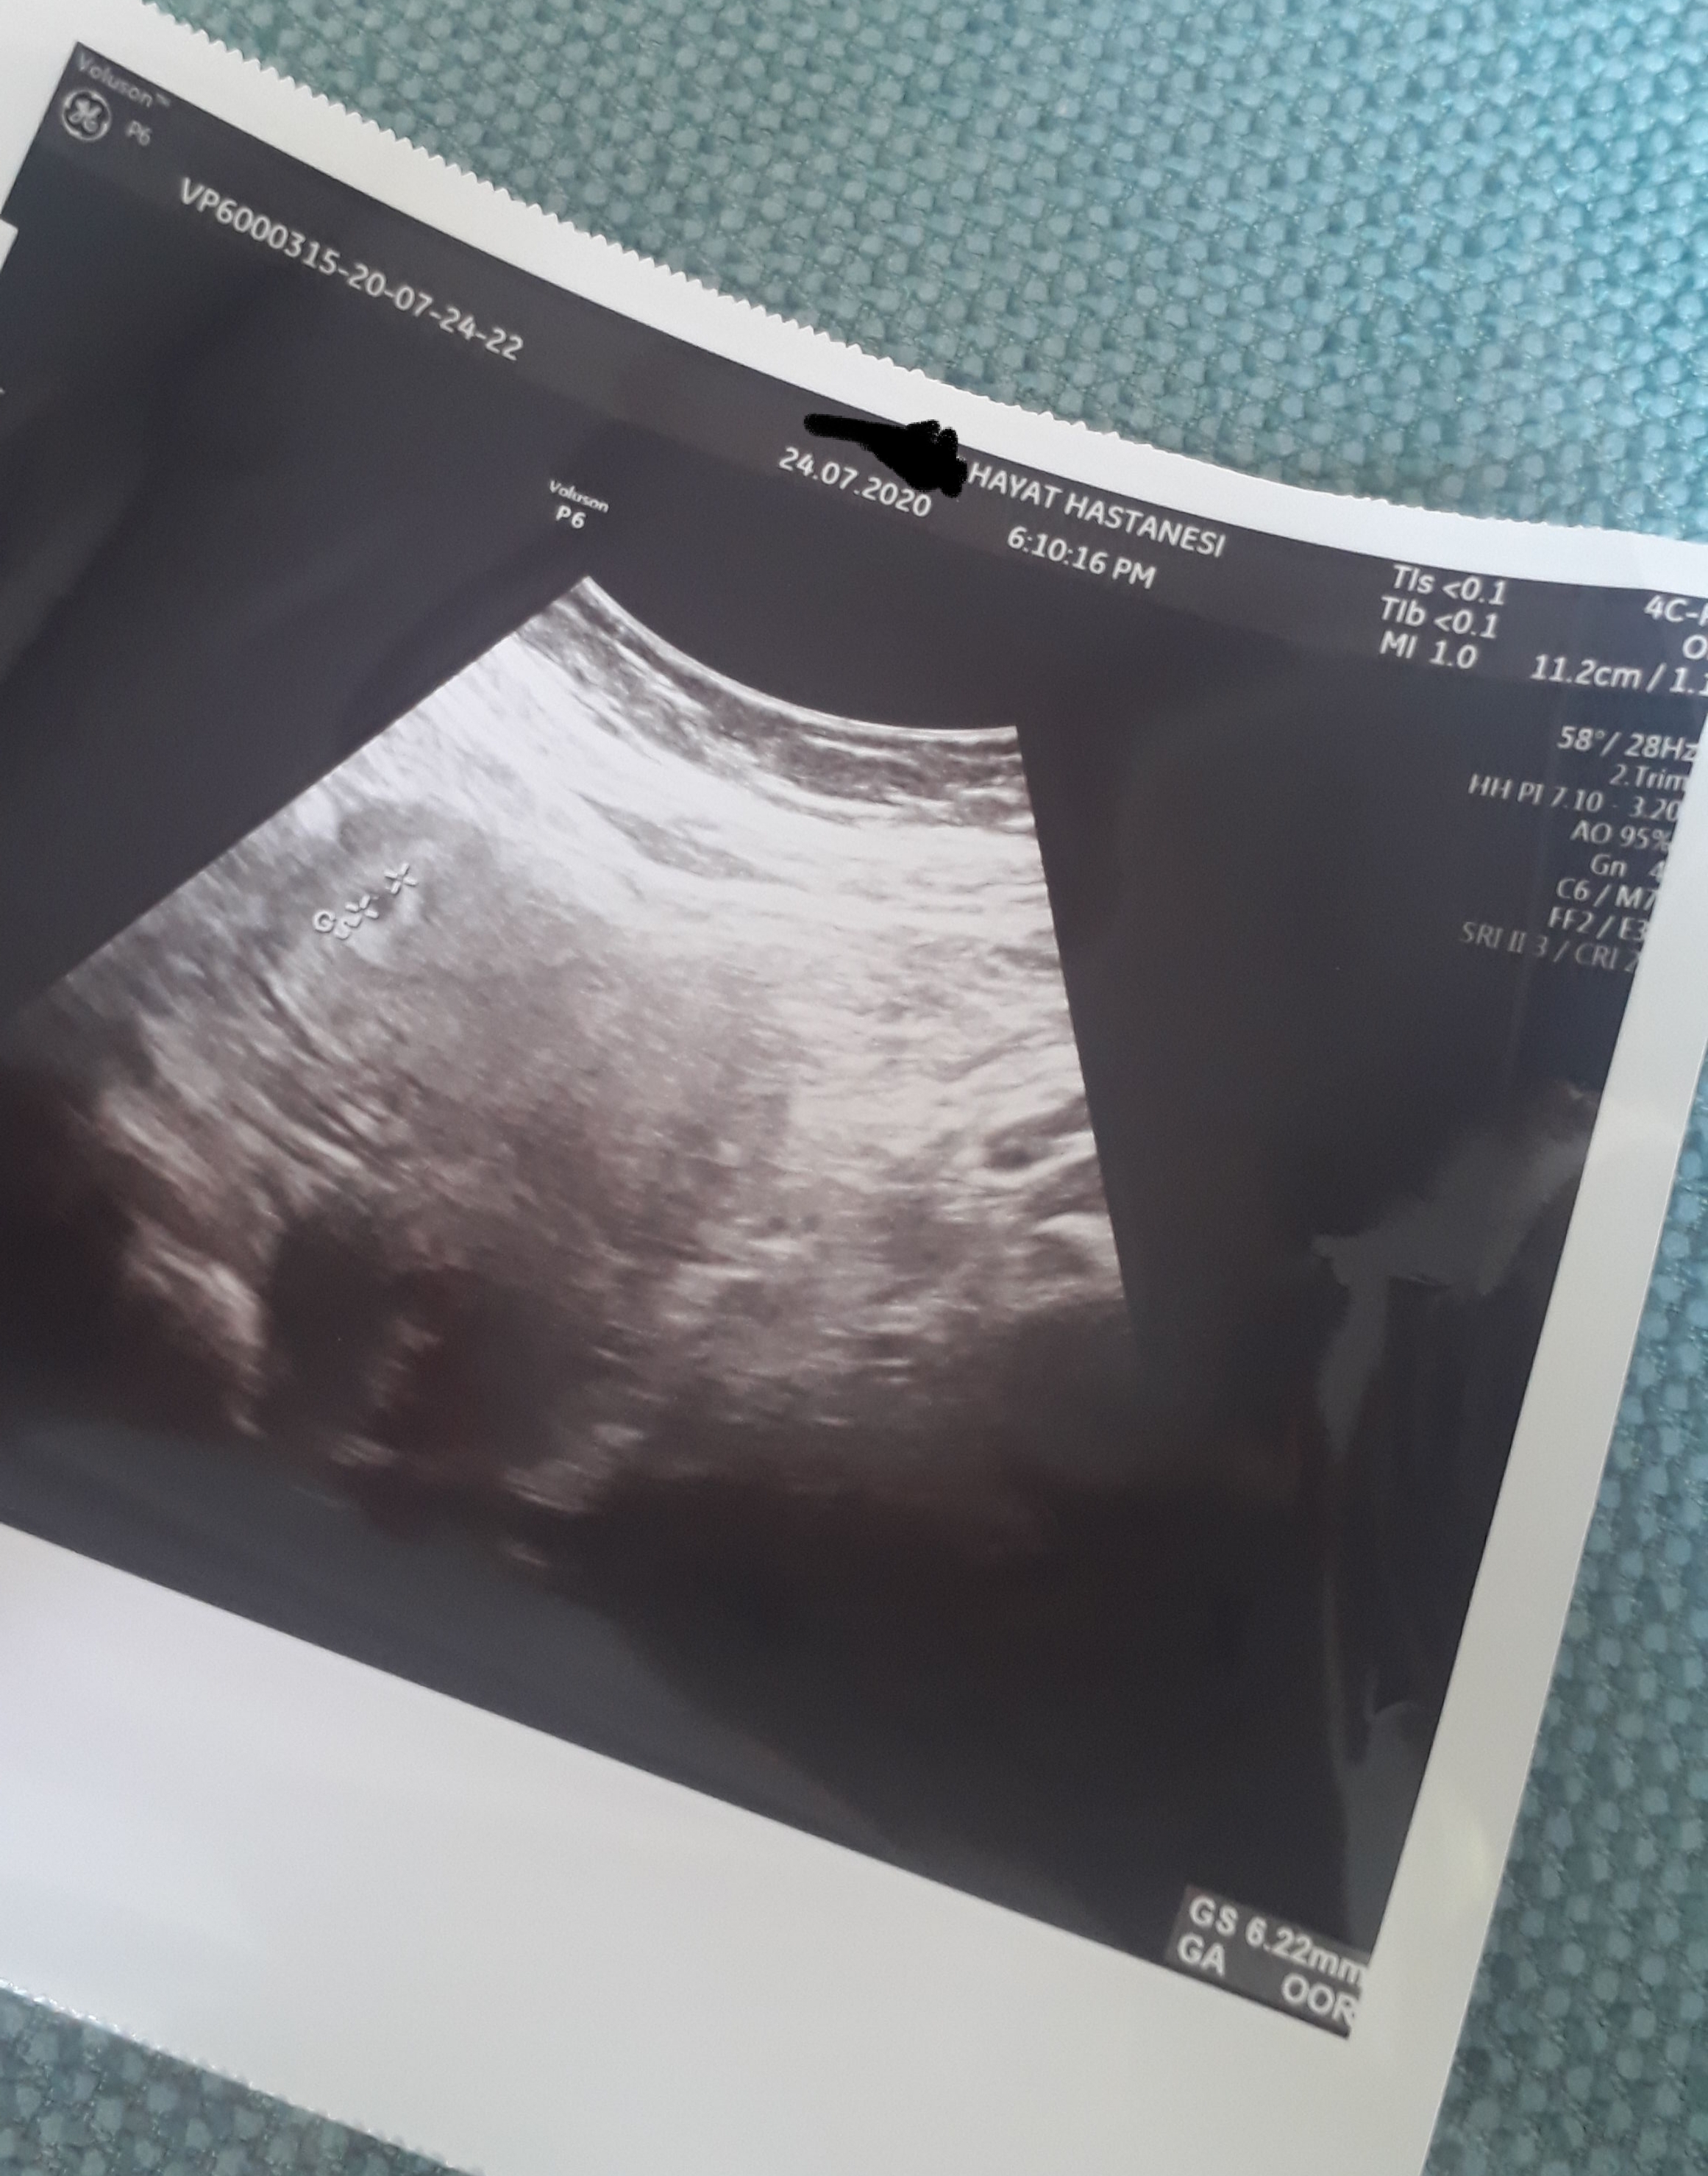

Hayatım sonuçların iyi güzel. İkişer gün ara ile iki katı artışın da tam yerinde keseyi görmen için henüz erken bu aralar sıkıntılardan streslerden ağır işlerden uzak dur. Allah'ın izni ile meleğin gelecek dünyaya. İyi düşün iyi olsun. Yüzde yüz hamilesin bu değerlerin sürekli artış göstermesi gerekiyor. Doktorun seni yönlendirecektir hayatım.